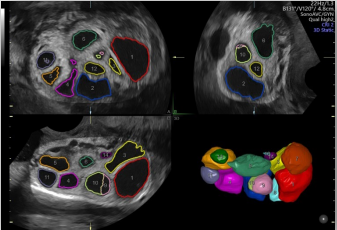

作為超聲領(lǐng)域的領(lǐng)導(dǎo)者,GE醫(yī)療一直走在全球前列。從世界第一臺A型超聲、第一臺實時B型超聲、第一把腔內(nèi)探頭、第一臺3D/4D超聲……一代代的經(jīng)典由此誕生,Voluson超聲也成為了婦產(chǎn)領(lǐng)域的代名詞。

Voluson內(nèi)置自動化技術(shù)幫助醫(yī)生精簡工作流程,減少擊鍵次數(shù);同時提高了測量的一致性和可重復(fù)性,推動檢查效率。

生長指標(biāo)半自動測量

在合適切面下,可自動識別測量臨床所需的胎兒雙頂徑,頭圍,腹圍,股骨長和肱骨長度等多個參數(shù)。

卵泡自動監(jiān)測

能夠自動計算受激卵泡數(shù)量和體積并排序,幫助快速識別優(yōu)勢卵泡。

通過自動的放置取樣框綠線并根據(jù)胎兒活動自動調(diào)節(jié),使得容積圖像的獲取更簡單快速。

智能NT和智能IT

胎兒頸后透明層/顱內(nèi)透明層標(biāo)準(zhǔn)化測量,減少主觀因素差異。